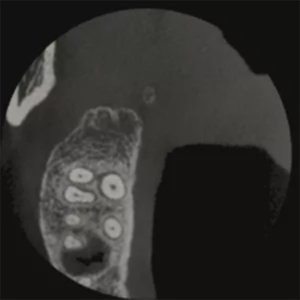

T-MAR Metal Artifact Reduction in LargeV Dental CBCT

With the new T-MAR module, the system automatically removes metal artifacts and corrects image distortions intelligently.

Hence, the final images remain clear, accurate, and clinically reliable.